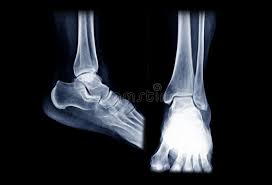

Exames de Imagem de entorse do tornozelo:

Em alguns casos, exames de imagem, como radiografias, ultrassonografia ou ressonância magnética, podem ser necessários para descartar fraturas ou avaliar melhor a extensão da lesão ligamentar.